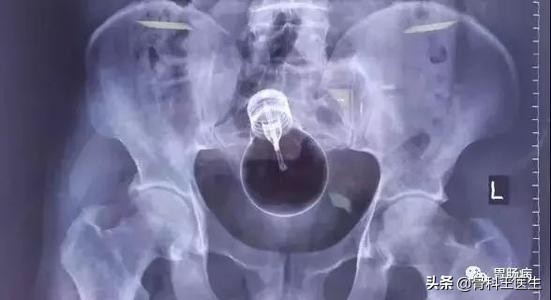

看到了没?自行车手把!

当时没有拍摄,取出的东西送病理去了,和上图差不多!

我的天呐!你没有看错,就是这个东西,我居然是把肚子切开,从病人的肠子里掏出来的!